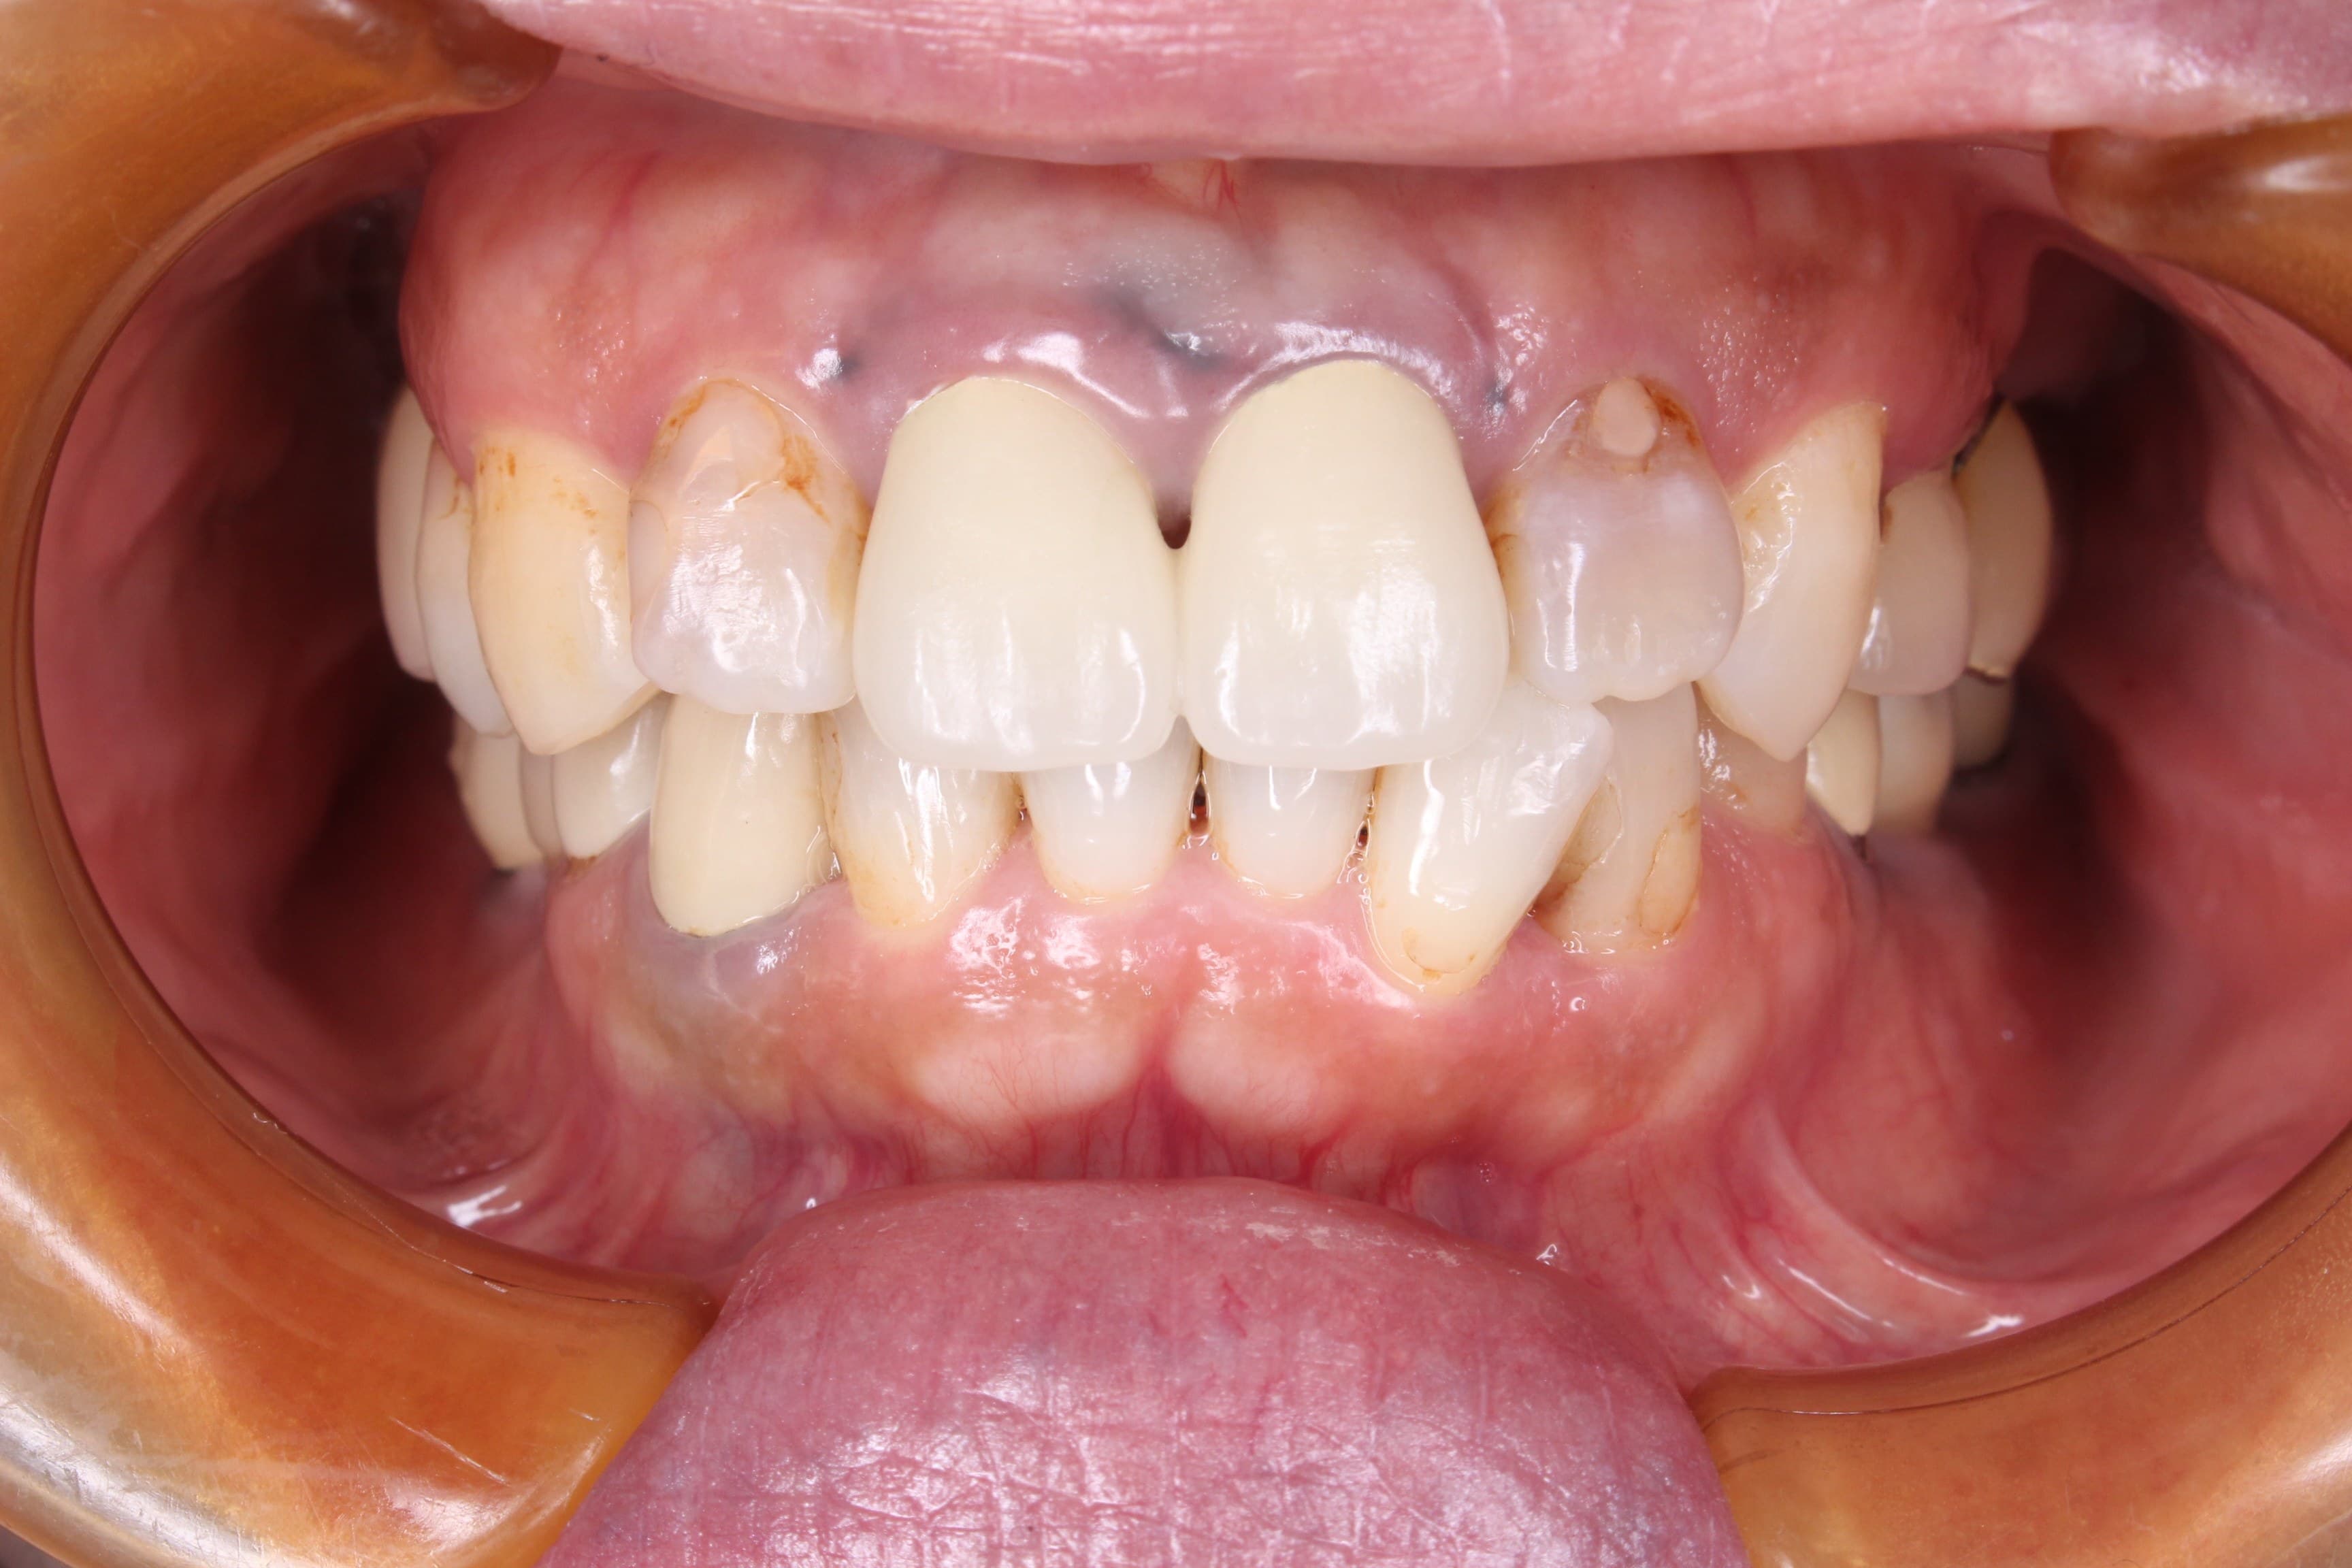

(初診時の口腔内写真)

奥歯にインプラントを行っていることから、徹底した炎症のコントロールが必要ですが、残念ながら歯周病に感染しており、芳しくない事実をお伝えし、その改善のため、歯周専門治療を受けて頂く事になりました。

治療終了時には、以前までのご自身の口の状態が悪かった事を実感され、良くなったことについて非常に驚いていらっしゃいました。